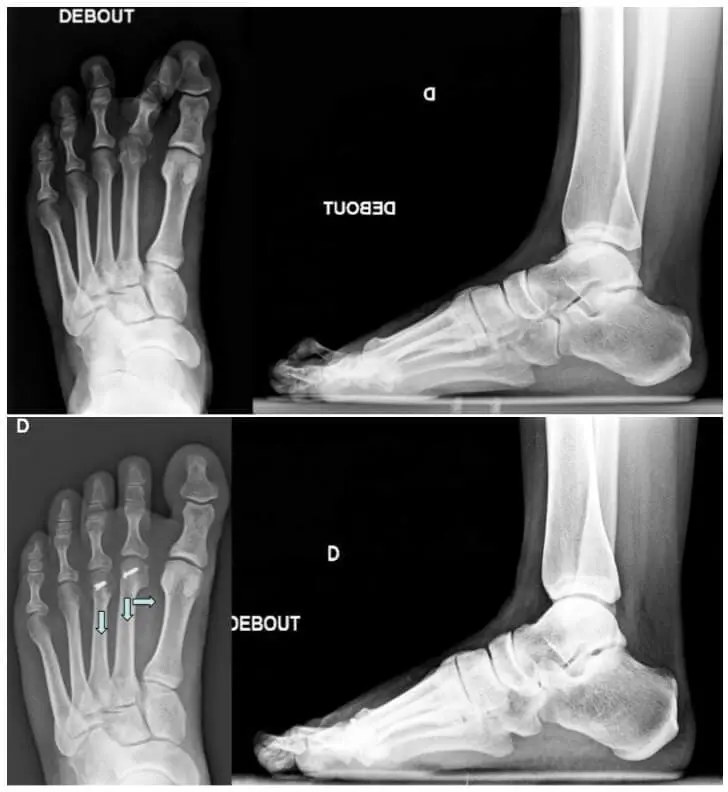

- The most common procedure is an osteotomy, in which the metatarsal bone (one or several), responsible for the overpressure, is relieved by making it a few millimetres shorter, or by slightly lifting it up. After such an osteotomy, a screw is usually placed, to make sure that the predetermined shortening is maintained. After the operation, one may in fact immediately lean on a specifically designed postoperative shoe.